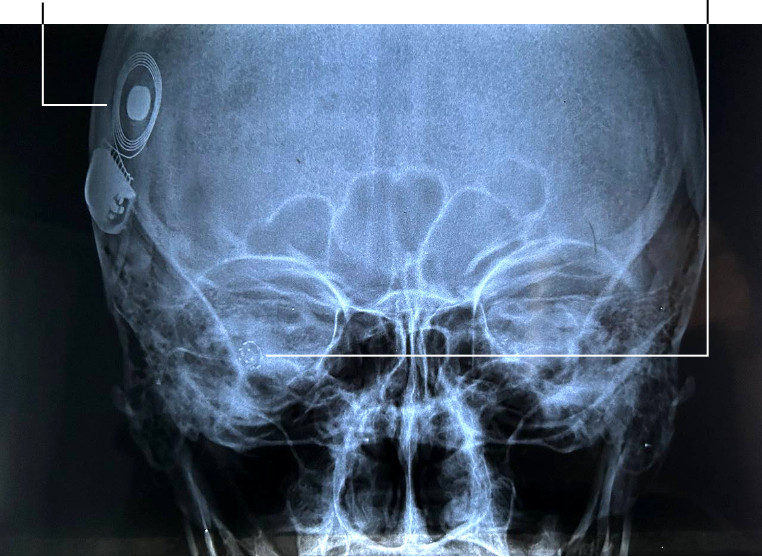

После операции функции моих погибших клеток взяли на себя четыре компонента кохлеарного имплантата:

- микрофон, который улавливает звук и преобразует его в электрический сигнал;

- процессор, который разбивает полученный сигнал по диапазонам частот;

- приемник, который передает раздробленный по частотам сигнал на электроды;

- электродная матрица из 8–22 электродов, которая сворачивается спиралью по улитке внутреннего уха.

Работа кохлеарных имплантатов опирается на логику частотно-зональной теории слуха. При этом электроды преимущественно располагаются в нижних поворотах улитки, где теория работает. До верхушки, где зональное кодирование, возможно, дает сбой, электроды доходят редко. Матрица вставляется так, что различные волокна слухового нерва стимулируются от электродов в разных зонах улитки: электроды у основания передают высокочастотные сигналы, электроды ближе к вершине — низкочастотные.